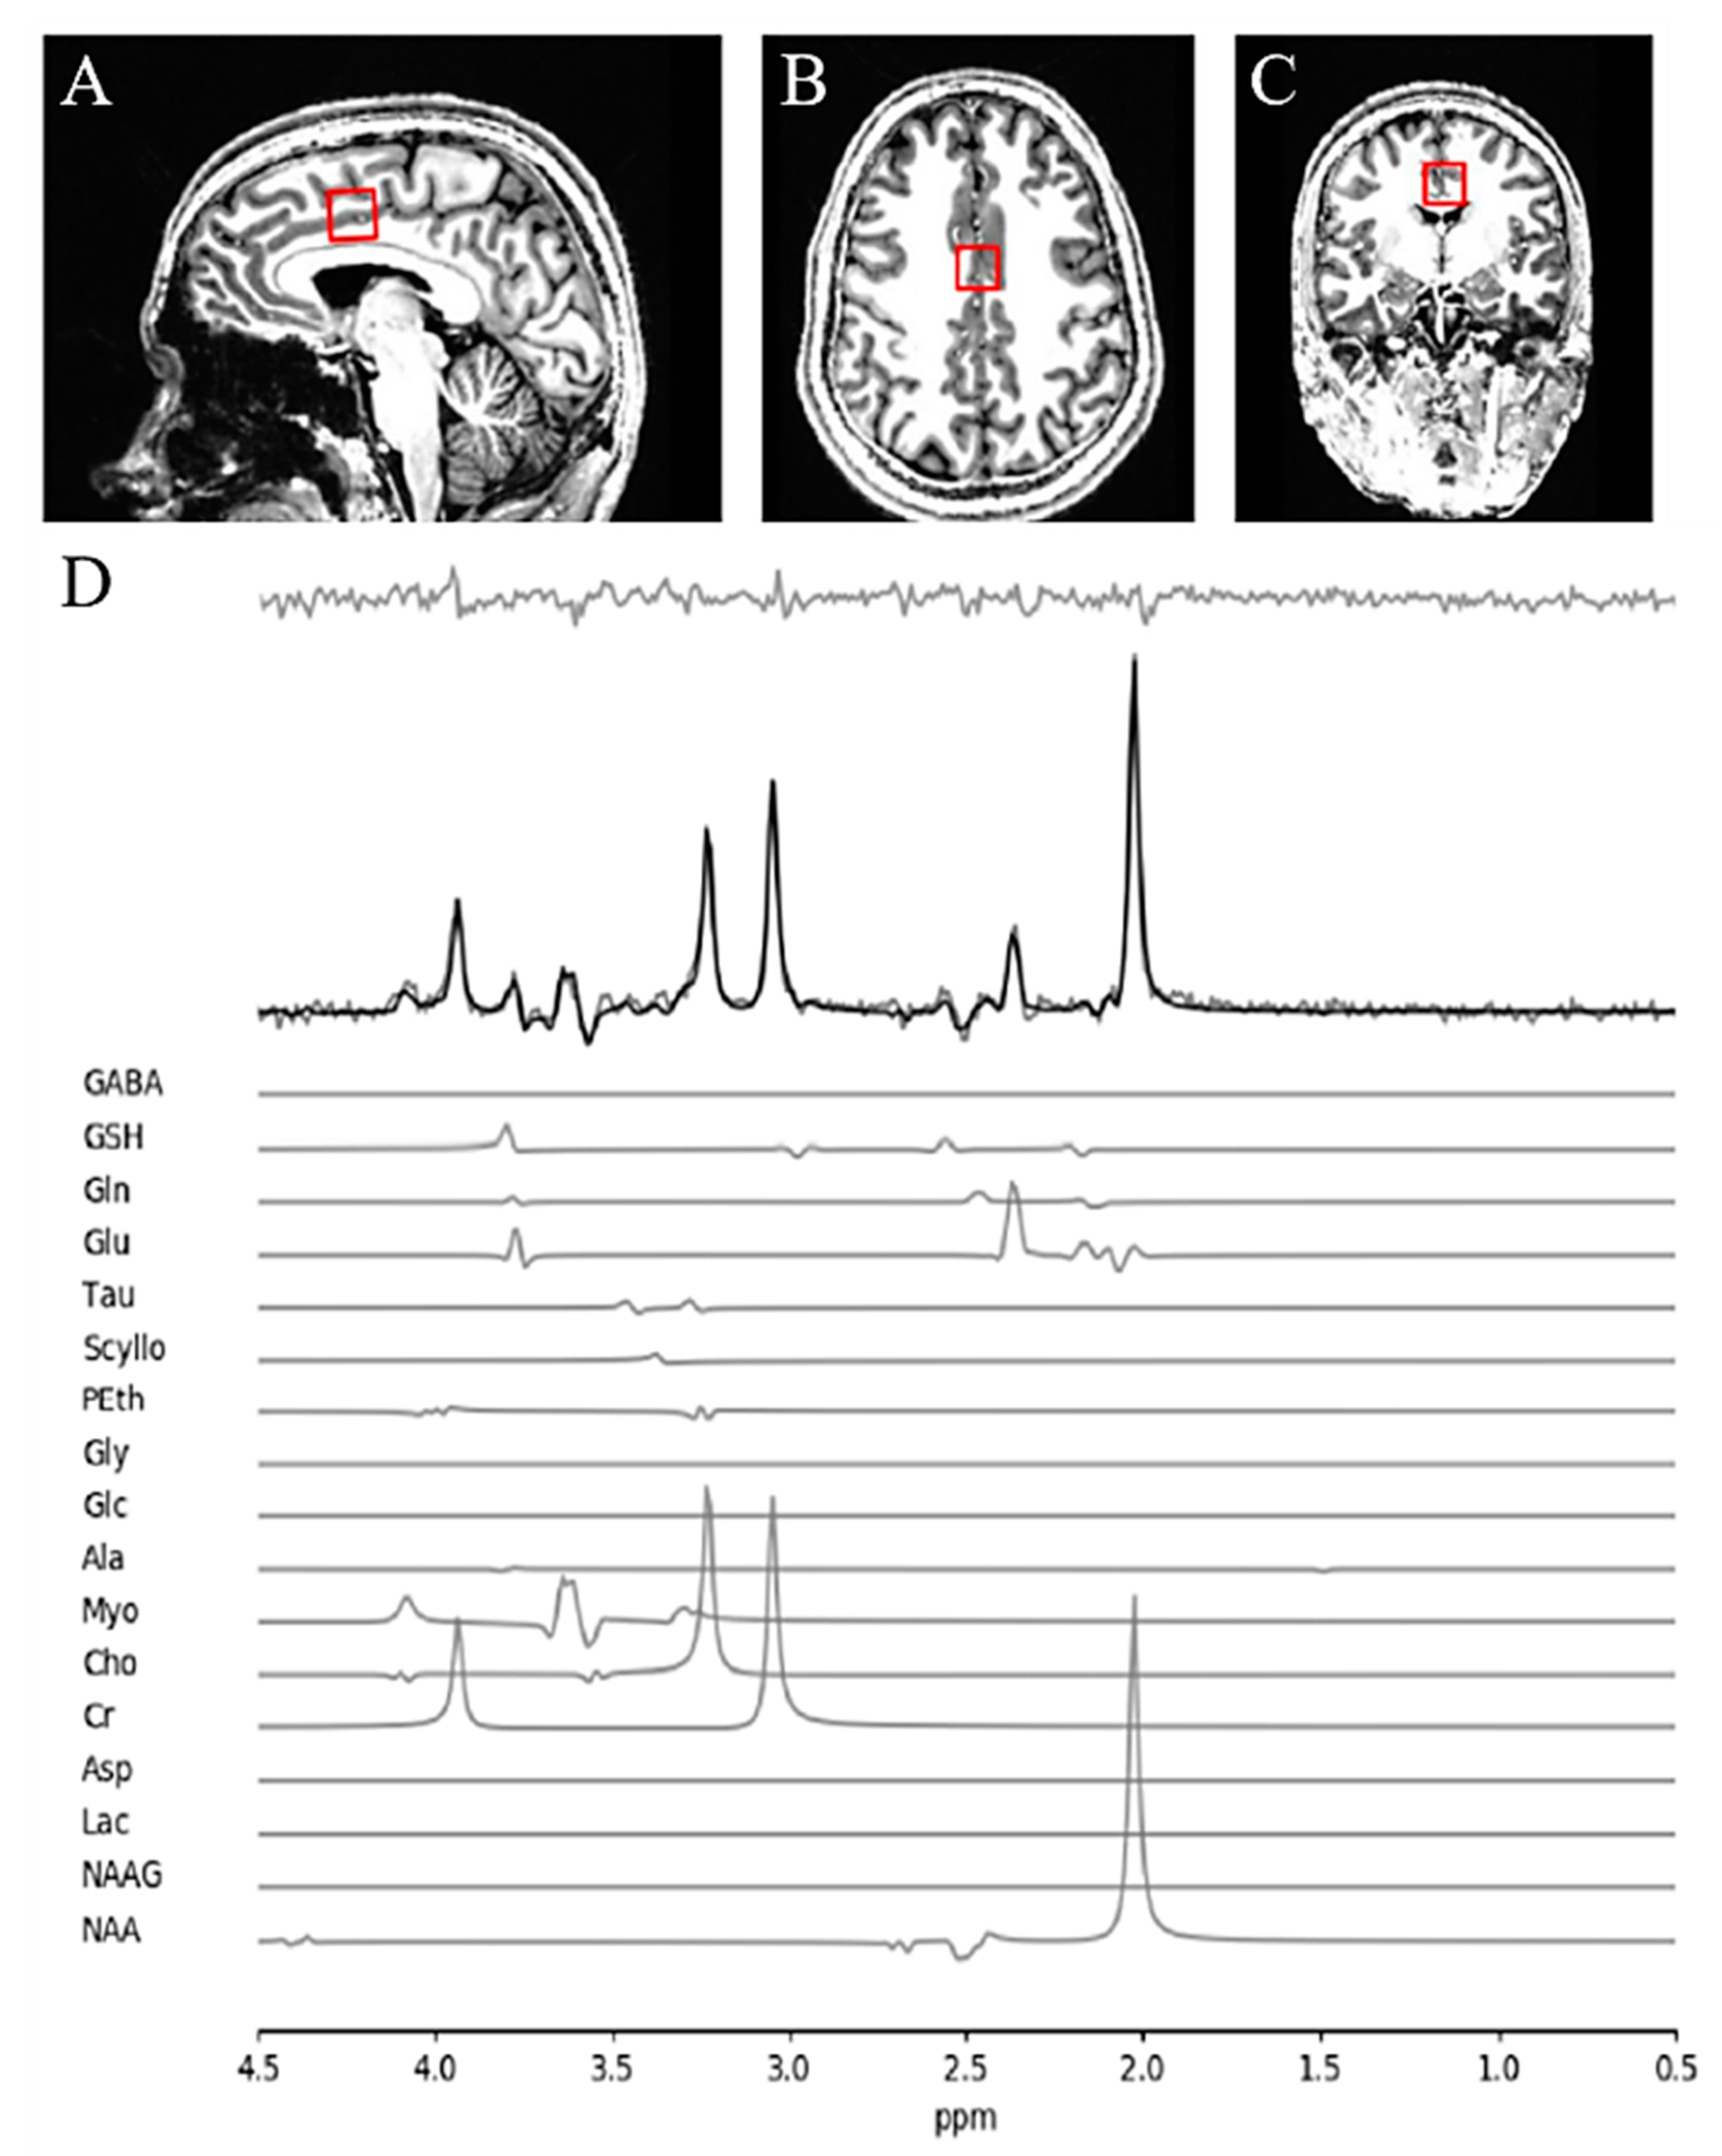

2.2. Magnetic Resonance Spectroscopy (MRS) Acquisition and Analysis